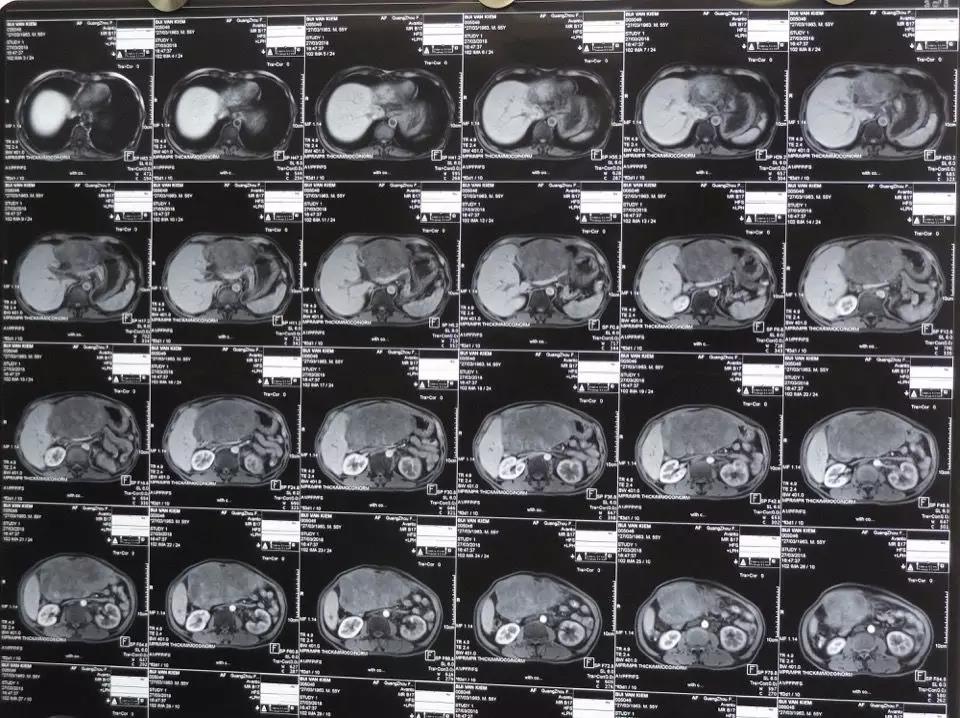

術前CT檢查圖。

但是,手術的復雜和困難程度也擺在眼前:“患者體重只有43公斤,且有多年乙肝病史,肝功能較弱,巨大的肝腫瘤約有14*10厘米大小,屬於肝左葉外生型肝癌,並且壓迫胃、結腸與胰腺,還侵犯至周圍臟器、血管,與周圍組織有多處粘連,手術難度極大。”其次,患者過去曾做過膽道手術,這無疑更增加了手術中剝離粘連的困難。穆峰博士告訴筆者,手術稍有不慎,患者就有可能命喪手術臺。

為此,王建南教授與穆峰博士壹起與手術團隊進行了多次術前討論,研究,采用電腦三維軟件對手術進行預切除評估,準備多個詳細的手術方案,對手術中可能出現的狀況進行預估,也與患者及家屬進行充分溝通。“預計到術中出血的問題,我們在術前調配了2000毫升備血。”穆峰說。